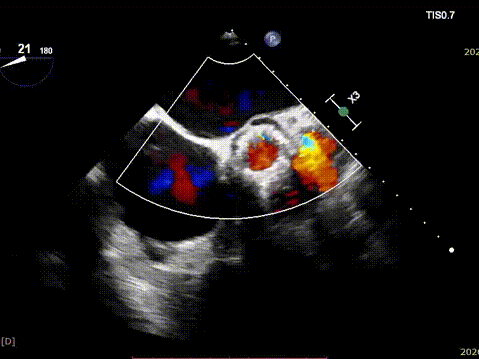

2026年伊始,TaurusTrio经导管主动脉瓣系统在复旦大学附属中山医院,浙江大学医学院附属第二医院,中国医学科学院阜外医院,首都医科大学附属北京安贞医院,四川大学华西医院等多家临床中心成功开展上市后全国首批植入。这不仅是TaurusTrio正式走向广泛临床应用的重要里程碑,更标志着中国单纯主动脉瓣反流介入治疗正式迈入了“心键合璧”的全新纪元。